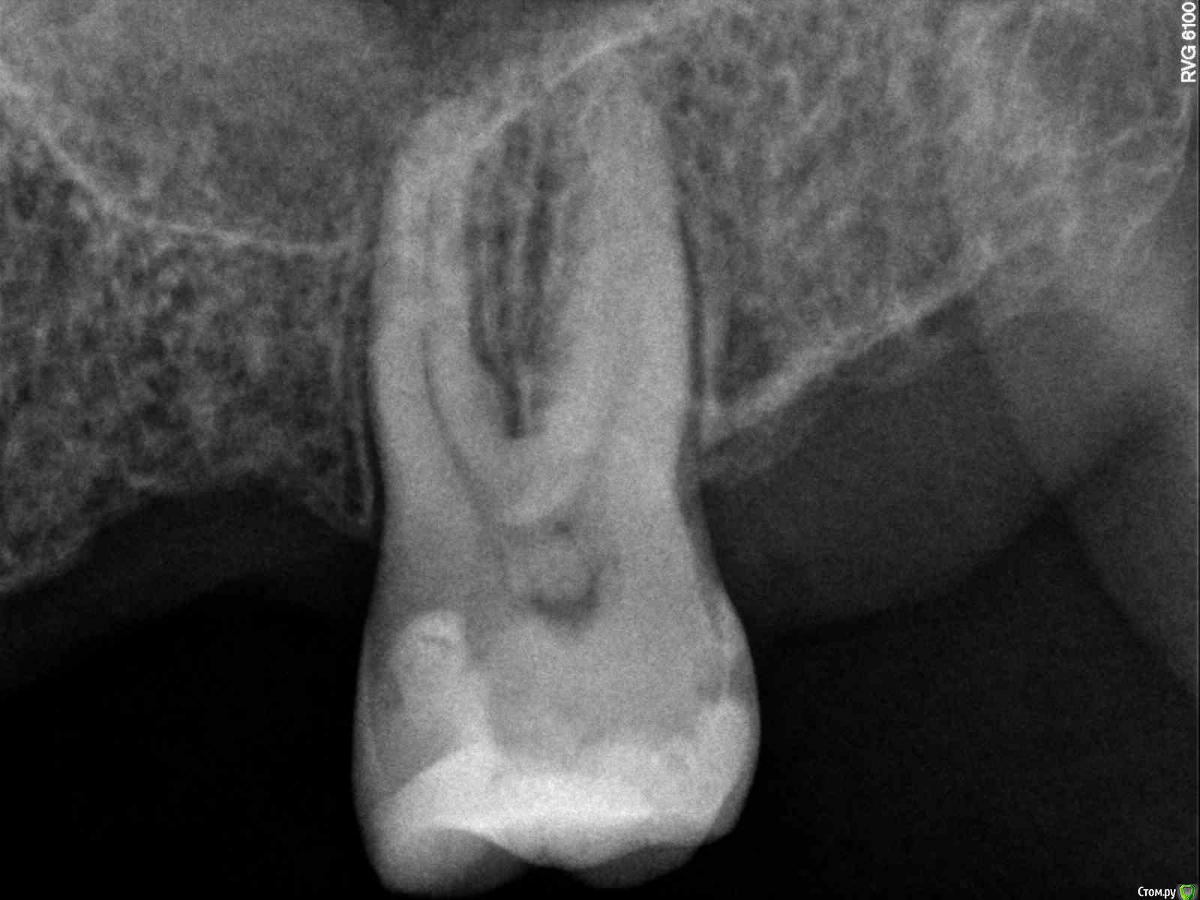

dsfksdkf Опубликовано 12 августа, 2015 Поделиться Опубликовано 12 августа, 2015 (изменено) Был у хирурга, терапевта - проблему видят - говорят "расширена перидонтальная щель с одной стороны" - в этом месте как раз и болит (еще там немного оголен зуб и круговые связки в этом месте возможно разорваны манипуляциями ранее и не восстанавливаются)но предложить ничего не могут Изменено 12 августа, 2015 пользователем dsfksdkf Ссылка на комментарий

Stomart Опубликовано 12 августа, 2015 Поделиться Опубликовано 12 августа, 2015 Надо проверить "живой" зуб или нет. Судя по снимку возможен пульпит/периодонтит. Ссылка на комментарий

dsfksdkf Опубликовано 12 августа, 2015 Автор Поделиться Опубликовано 12 августа, 2015 (изменено) Вот в этом месте болит - черное в кости это что? С другой стороны по другому Изменено 12 августа, 2015 пользователем dsfksdkf Ссылка на комментарий

dsfksdkf Опубликовано 12 августа, 2015 Автор Поделиться Опубликовано 12 августа, 2015 Рассматривая фото я вдруг понял - связок в этом месте (белого) почти нет - хотя с другой стороны есть Ссылка на комментарий